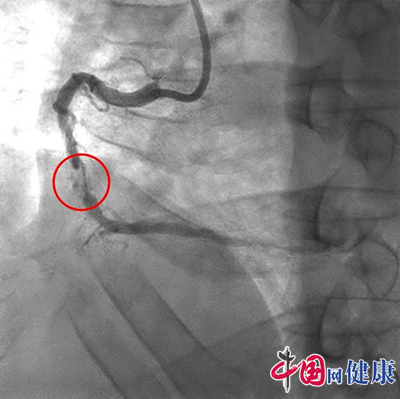

温先生数月前活动后突发胸闷痛,反复头晕胸痛到中山大学附属第五医院就诊,医生诊断考虑不稳定型心绞痛,冠状动脉造影检查发现该患者右冠状动脉中段重度狭窄,严重钙化,狭窄程度达95%。

术前右冠状动脉重度阻塞